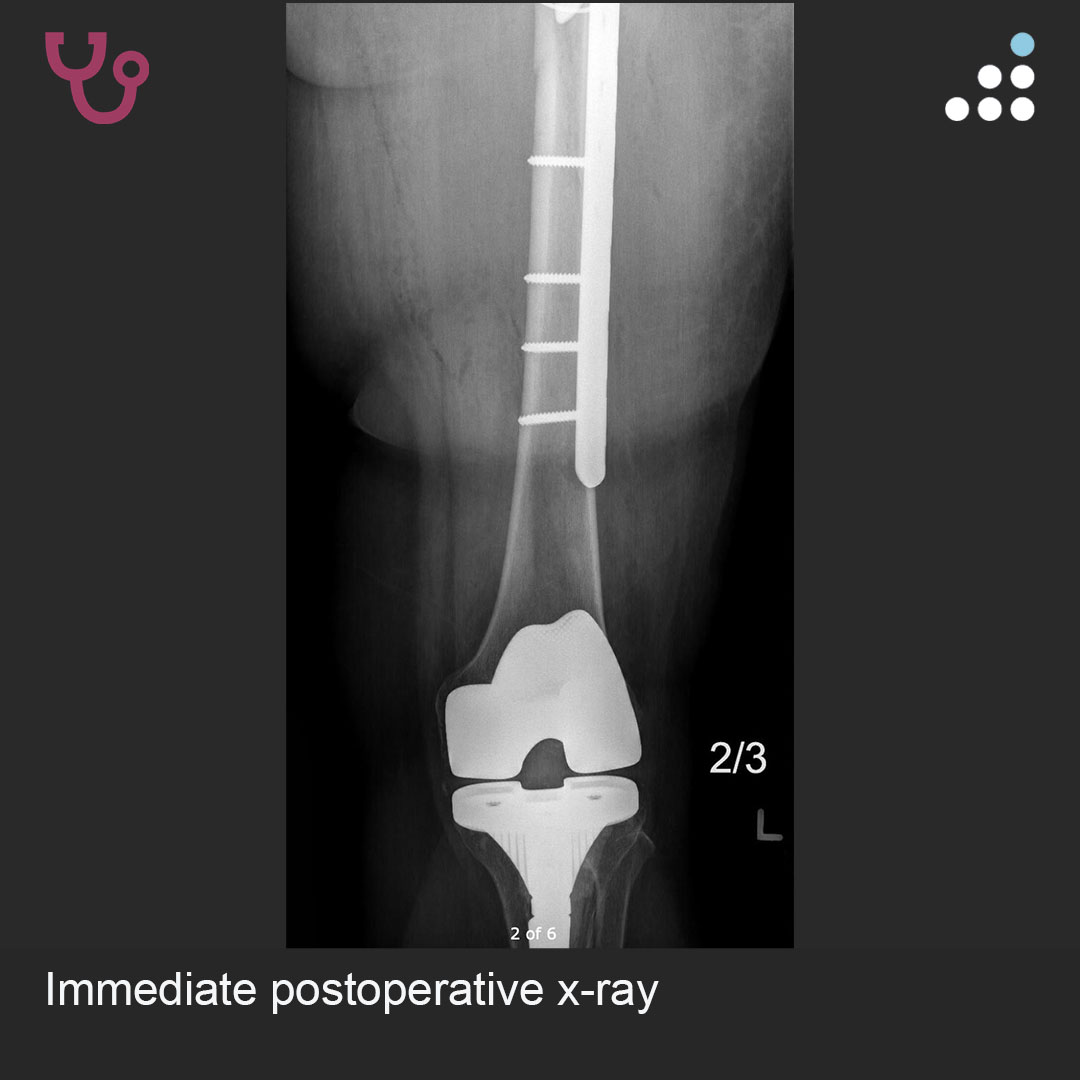

Can you answer our free question of the day? A patient presents to the trauma bay after involvement in a motor vehicle collision. Radiographs obtained in the trauma bay demonstrate a right distal femur fracture, as seen in Figure A. In surgery, the articular block is reduced, and reduction is held with headless compression screws. A retrograde intramedullary nail is then placed. After nail advancement, a varus and recurvatum deformity is noted at the fracture site with intraoperative fluoroscopy, as demonstrated via illustrations in Figures B and C. Placement of blocking screws in which locations (A - H) from Figure B and C would help correct this deformity? 1. B + E 2. A + G 3. B + F 4. C + H 5. D + H QID: 217509 Comment your answer below, then check to see if you got it correct by clicking the link below to see the answer & explanation. bit.ly/3OxP8sP #orthopedics #orthopedicsurgeon #orthopaedics #orthopaedic #orthopedic #ortholife #orthobullets #orthoresidents #orthoresident #orthoresidency #medicalschool #medicalstudent #medstudent #doctor